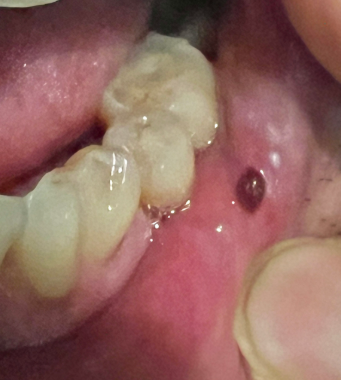

입안에 생긴 피물집, 괜찮은 걸까?

갑작스러운 피멍울, 원인부터 대처법까지 총정리

색이 검붉거나 자주빛을 띠고,

손으로 만져보면 말랑하고 물집처럼 부풀어 있기도 하죠.“이거 혹시 암 아니야?”

피물집이란 말 그대로 혈액이 얇은 점막 아래에 고여 생긴 물집 또는 멍울을 말합니다.

의학적으로는 ‘혈종’(Hematoma) 혹은 경우에 따라 ‘점액낭종’(Mucocele) 등으로 분류됩니다.보통은 통증 없이 말랑하고,

작은 혹처럼 볼록 튀어나오며,

색은 검붉거나 자주색, 때론 투명한 경우도 있어요.